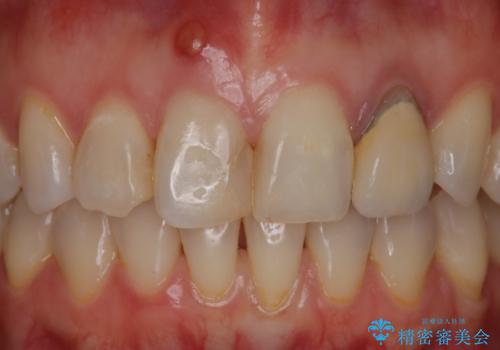

- 患者様は前歯にできものができたということで来院されました。

歯髄診断を行い、失活していると判断して根管治療を行いました。